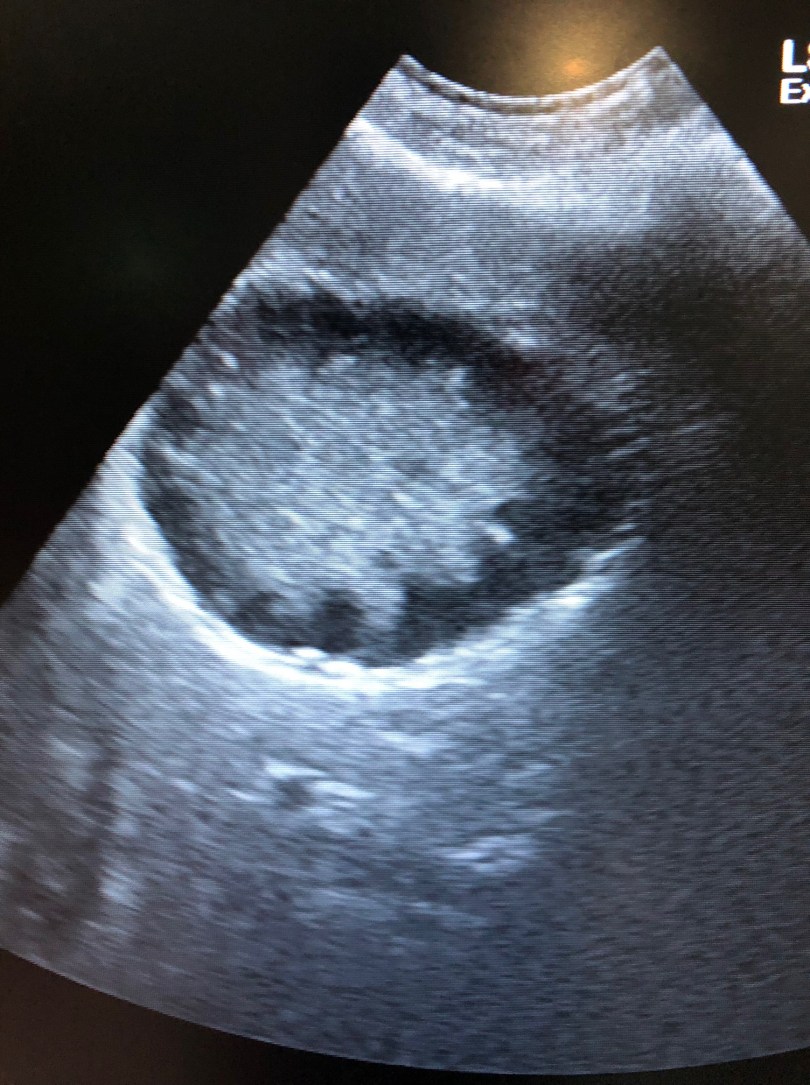

上の写真はキウイフルーツの滑面ではありません。。。

超音波検査で認められた胆嚢の画像です。正確には、胆嚢粘液嚢腫という病気の超音波画像になります。胆嚢粘液嚢腫とは、胆嚢内にゼリー状の粘稠性が高い物質が長い期間沈殿し、胆嚢を拡張させ、非常に硬化させてしまう病気です。胆嚢粘液嚢腫は胆嚢自体にも重篤な炎症や感染を引き起こしますが、実は隣接する肝臓にも悪影響を引き起こす厄介な病気でもあります。